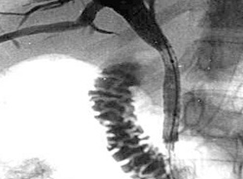

En cas d’ictère ou « jaunisse », il faut souvent réaliser une CPRE avec pose de prothèse biliaire par voie endoscopique. Ce geste permet de libérer la bile qui peut s’écouler dans le duodénum et faire disparaitre l’ictère.